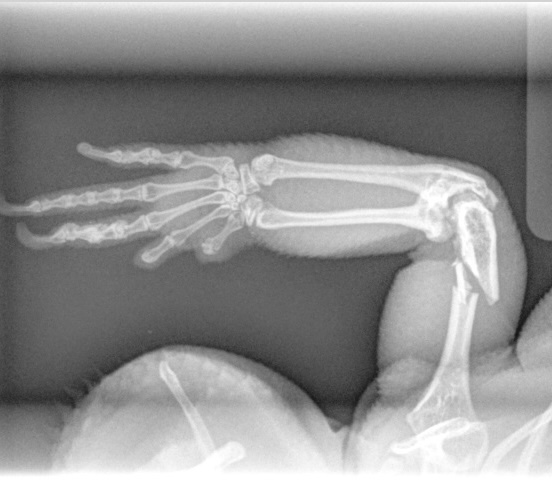

Fracture Repair

We provide surgical fracture repair for many types of broken bones. Treatment plans are individualized based on the location and complexity of the fracture, your pet’s age and size, and overall health.

Radius Fracture Before #1

Radius Fracture Before #2